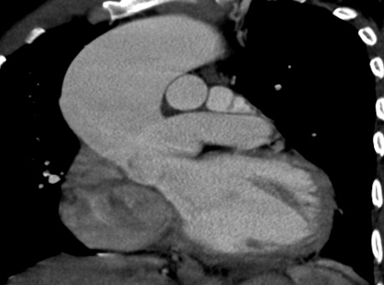

Persistent truncus arteriosus is an uncommon complex congenital heart disease. Without surgical intervention, the prognosis is not good. Very few untreated cases of truncus arteriosus survive to maturity. We report an exceptional case of uncorrected truncus arteriosus surviving into adulthood of type a3 variant -van praagh classification as a 26-year-old male who had well tolerated dyspnea since birth. Our patient showed a single(right) pulmonary artery arising from the common arterial trunk supplying the right lung and absent main and left pulmonary artery with collateral supply to the left lung consistent with the truncus arteriosus type a3-van praagh classification